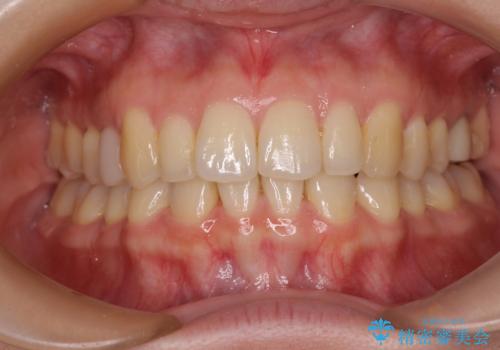

先天欠損のある歯列 インビザライン矯正

- 上顎前歯の突出感を気にして来院された患者様です。

下顎前歯2本が先天欠損しており、上顎歯列に対して、下顎歯列がアンバランスに小さい状況でした。

左右上顎側切歯2本が矮小歯であるため、上顎の抜歯ではなく、IPR(歯と歯の間を削る)と歯列全体の後方移動によってバランスを整えることとしました。

歯列のバランスが悪く、インビザライン矯正特有の奥歯の噛みにくさがなかなか改善されず、治療期間が長期化してしまいました。